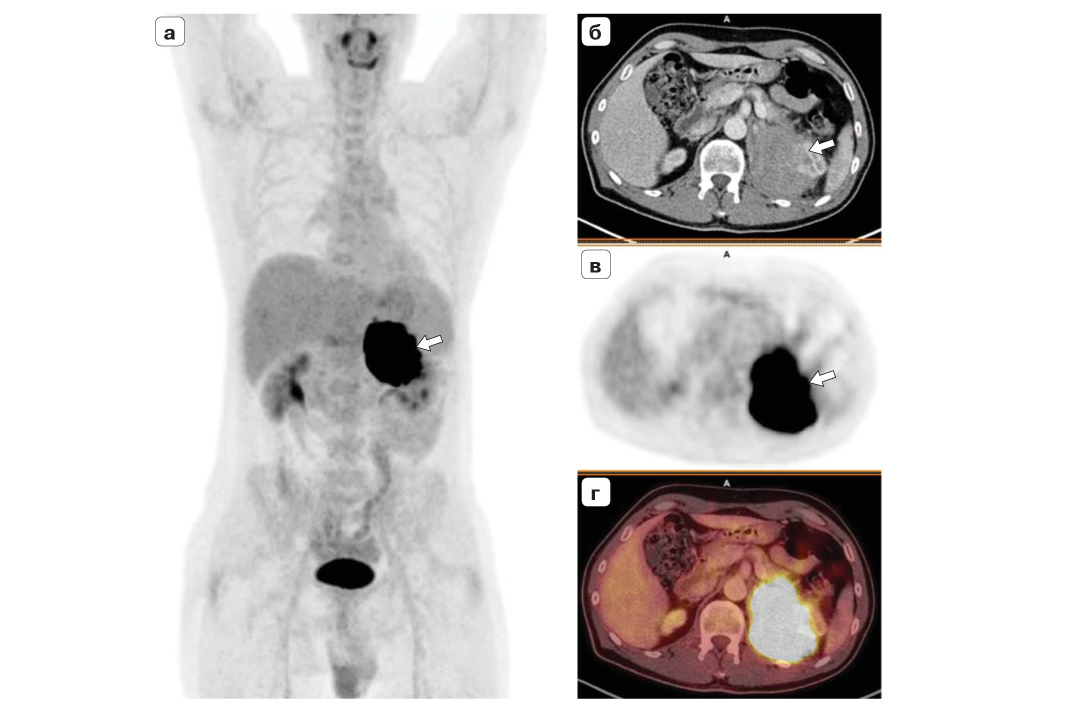

По результатам ПЭТ/КТ-исследования c 18F-ФДГ от 31.07.2014 у пациента в ложе левого надпочечника выявлено солидной структуры объемное образование с неровными контурами размерами 8,9 × 5,9 × 7,2 см, с SUVmax до 33,27. Образование врастает в верхний полюс левой почки без инвазии ее сосудистой ножки, в хвост поджелудочной железы, левую ножку диафрагмы, селезенку и селезеночную вену. Других участков патологического накопления 18F-ФДГ не обнаружено (рис. 1).

Рис. 1. Рецидив адренокортикального рака после адреналэктомии. ПЭТ/КТ-исследование с 18F-ФДГ. ПЭТ (MIP) во фронтальной проекции (а), КТ с внутривенным контрастным усилением (б), ПЭТ- (в) и ПЭТ/КТ- (г) изображения в аксиальной проекции. Стрелками отмечено объемное образование в ложе левого надпочечника с признаками выраженного накопления РФП (SUVmax 33,27).

1. Рис. 1. Рецидив адренокортикального рака после адреналэктомии. ПЭТ/КТ-исследование с 18F-ФДГ. ПЭТ (MIP) во фронтальной проекции (а), КТ с внутривенным контрастным усилением (б), ПЭТ- (в) и ПЭТ/КТ- (г) изображения в аксиальной проекции. Стрелками отмечено объемное образование в ложе левого надпочечника с признаками выраженного накопления РФП (SUVmax 33,27).